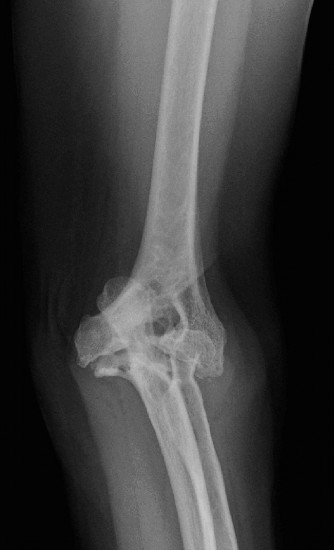

- Plain Radiographs: Anteroposterior (AP) and lateral views are essential. Obtain views of the entire humerus and forearm to assess overall alignment, bone stock, and presence of previous hardware. Look for characteristic RA changes: joint space narrowing, erosions (particularly radial head, capitellum, olecranon, trochlear notch), subchondral cysts, osteopenia, and subluxation/dislocation. Stress views may reveal instability.

- Plain Radiographs: Anteroposterior (AP) and lateral views of the elbow are fundamental. Obtain true AP and lateral projections. Evaluate for characteristic RA changes: diffuse joint space narrowing, articular erosions (radial head, capitellum, trochlear notch, olecranon), subchondral cysts, osteopenia, and joint subluxation or dislocation. Assess overall bone stock, particularly at the distal humerus and proximal ulna, which is crucial for implant fixation. Stress radiographs may be considered to evaluate ligamentous instability if not readily apparent clinically.